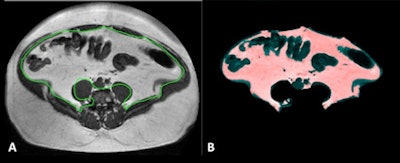

Above: MRI section of a 39-year-old patient, measured at the second and third lumbar vertebrae. The visceral fat is enclosed by the green line in A, and shaded pink in B. Sections of the large intestine are visible in the abdomen. Clinical images courtesy of Klinik für Diagnostische und Interventionelle Radiologie, Universitätsklinikum Leipzig. Below: MRI sections at the second and third lumbar vertebrae in two obese patients. Patient A had much more visceral fat (inside the green line) than patient B, but both had an almost identical body mass index of around 45 kg/m2.

Above: MRI section of a 39-year-old patient, measured at the second and third lumbar vertebrae. The visceral fat is enclosed by the green line in A, and shaded pink in B. Sections of the large intestine are visible in the abdomen. Clinical images courtesy of Klinik für Diagnostische und Interventionelle Radiologie, Universitätsklinikum Leipzig. Below: MRI sections at the second and third lumbar vertebrae in two obese patients. Patient A had much more visceral fat (inside the green line) than patient B, but both had an almost identical body mass index of around 45 kg/m2."Because of this correlation between abdominal fat and cardiovascular risk, it can be a good idea to use MRI to measure abdominal fat in overweight patients," explained Dr. Alexander Schaudinn of the diagnostic and interventional radiology clinic/IFB AdipositasErkrankungen at Leipzig University Hospital.